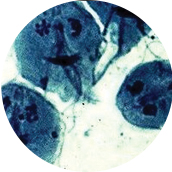

클라미디아 트라마티스(Chlamydia Trachomatis)라는 세균에 의한 성병입니다.

여성에게 감염 시 경한 하복부 통증과 비정상 자궁출혈을 보이나 증상이 없는 경우도 많습니다. 미국의 경우 클라미디아는 청소년과 성인에게서 가장 흔한 세균에 의한 성병입니다.젊은 여성의 10명 중 한 명은 클라미디아에 감염되어 있다고 보면 됩니다.

심한 난관 손상을 일으켜 불임을 일으킬 수 있으므로 철저히 치료 받아야 하며, 최근 불임이 증가하고 있는 가장 큰 이유가 클라미디아 때문이라는 보고도 있습니다. 그 밖에도 골반염, 방광염, 화농성 자궁경부염을 자주 일으키고, 워낙 증상이 없기 때문에 자주 검사를 받아보는 것이 제일 좋습니다.